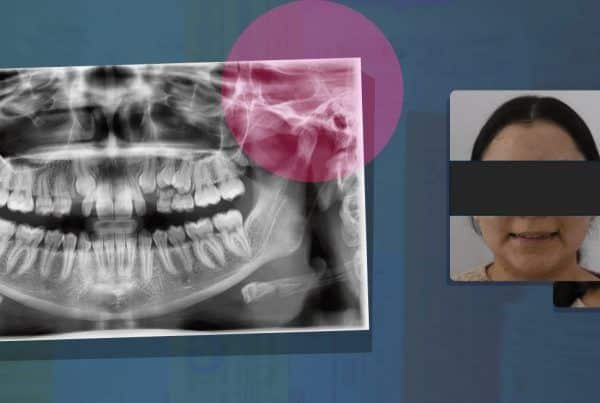

Paciente femenina de 43 años acude a consulta por un dolor difuso en la zona anterior izquierda del maxilar superior, refiriendo molestia por las noches y de forma aleatoria en el transcurso del día. Los hallazgos clínicos revelaron múltiples restauraciones de resina compuesta. El órgano dentario #22 resultó positivo a las pruebas pulpares. El examen radiográfico reveló una restauración extensa mal ajustada he infiltrada en la cara mesial, abarcando el tercio medio a incisal comprometiendo el complejo dentino pulpar. Con base a lo anterior se diagnostica una pulpitis irreversible. Fig. 1